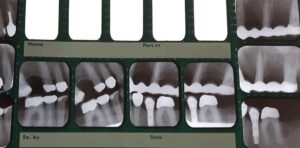

Tandvårdskortet

1 december, 2020

Tycker du att det är dyrt att gå till tandläkaren? För dig med en funktionsnedsättning, psykisk eller fysisk, kan det…